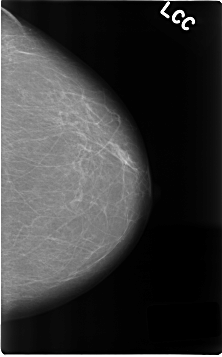

C_0190_1.LEFT_CC

LEFT_CC LINES 4632 PIXELS_PER_LINE 2880 BITS_PER_PIXEL 12 RESOLUTION 50 NON_OVERLAY